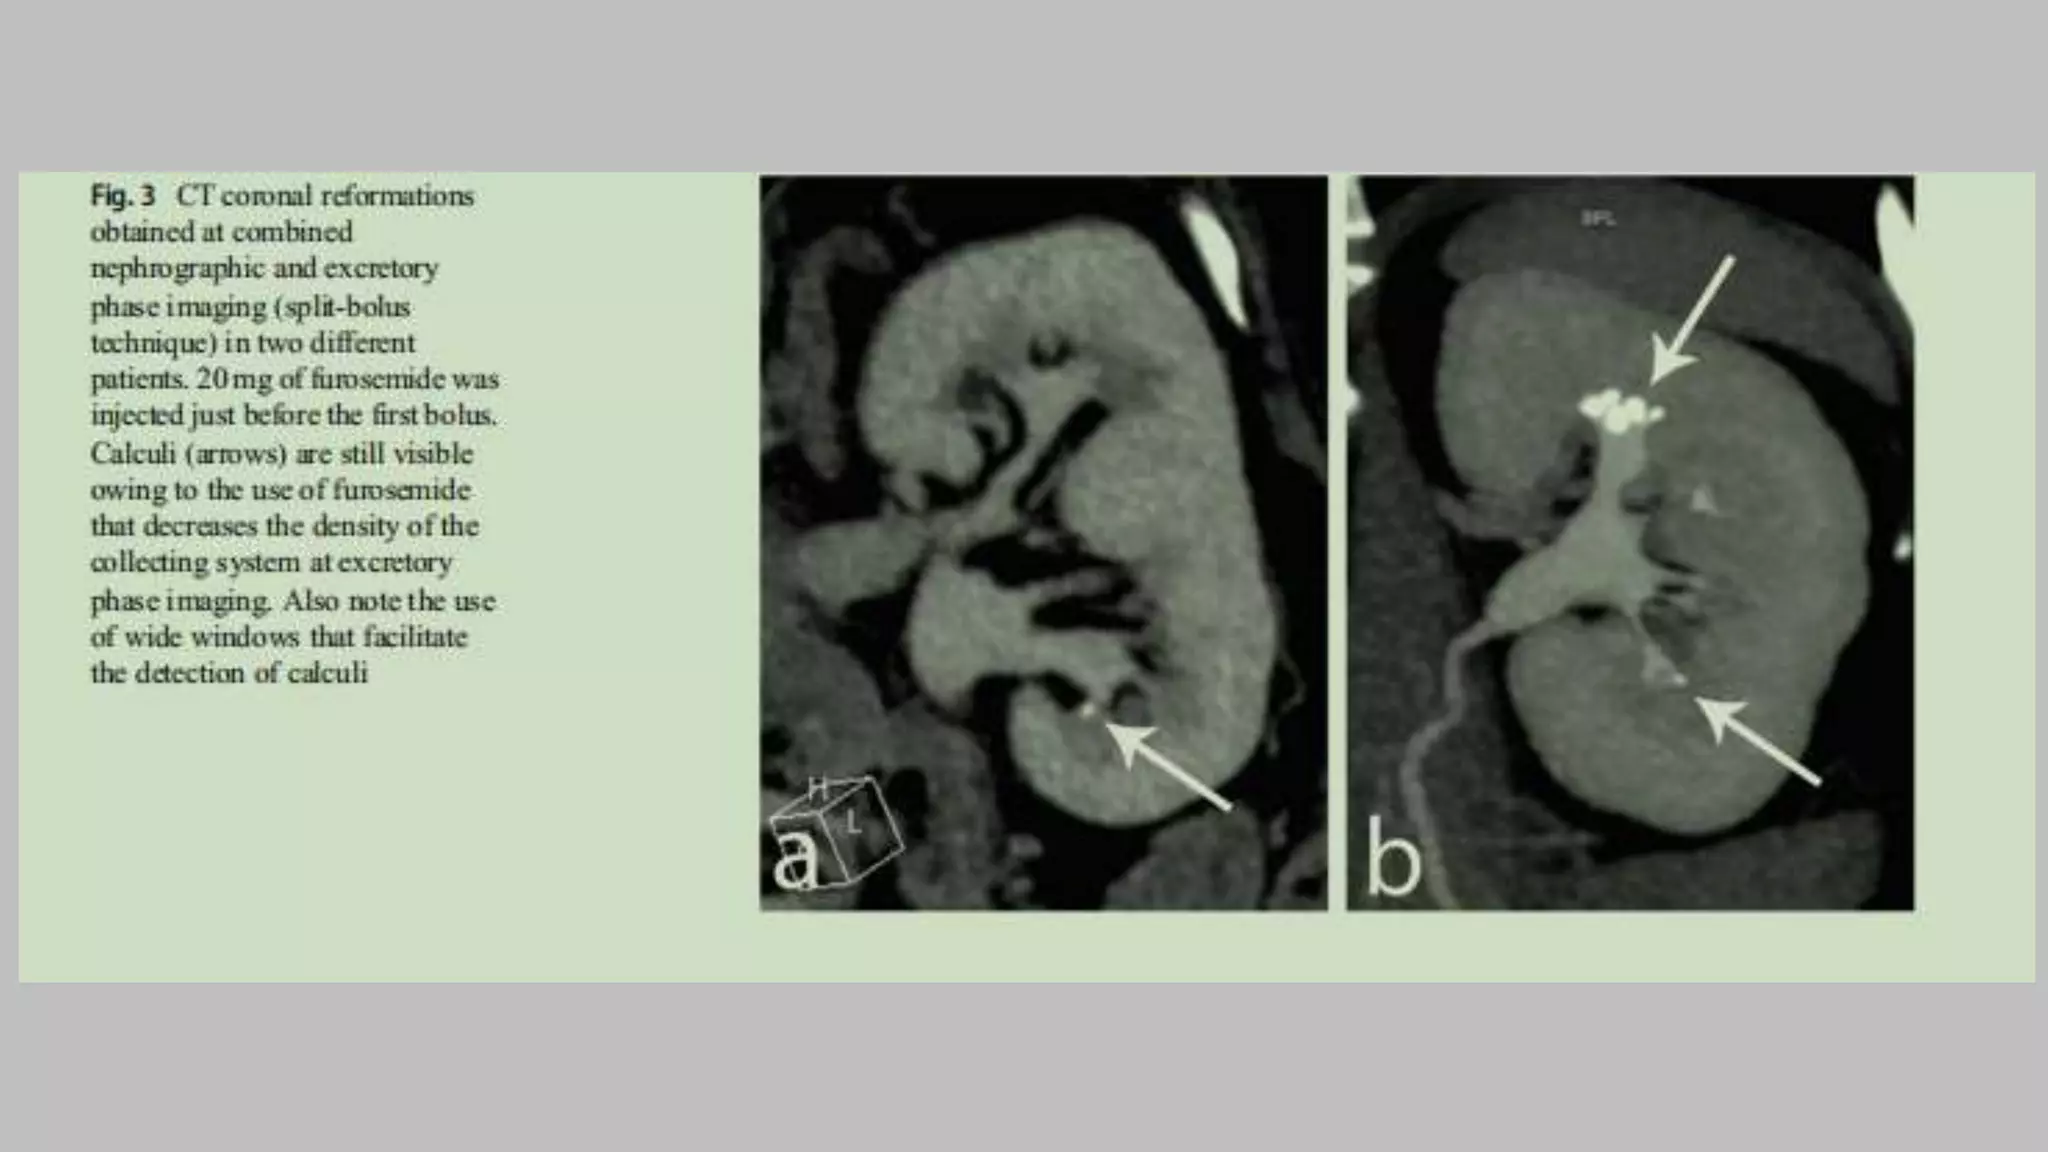

• Alternative techniques for achieving optimal visualization of the collecting

systems include supplemental use of normal saline infusion and diuretic injection.

• Nolte-Ernsting et al . reported that intravenous injection of low-dose diuretics (10

mg of furosemide) before intravenous contrast material injection also permitted

less dense, homogeneous opacification of the collecting systems compared to

supplemental infusion of 300 mL of normal saline.

Split-bolus technique

• generally done in DECT

• Radiation doses can be reduced with use of a split-bolus (two-phase) technique

• In which an unenhanced acquisition is followed by IV administration of 30–50

mL of contrast material, and a second bolus of 80–100 mL of IV contrast material

is given after an 8- to 10-minute delay, during which the acquisition is performed.

• Thus in a single nephropyelographic phase acquisition, the renal parenchyma

(nephrographic phase) and the collecting system, ureters, and bladder

(pyelographic phase) are assessed in a reduced the number of phases at a reduced

radiation dose.